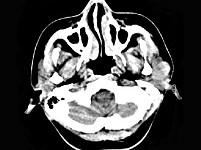

问题 女,28岁,左耳前肿块34月余,PE:左侧耳前可触及肿块,境界尚清、质硬、活动度尚可,CT如图所示,最可能诊断为()

选项 A.神经纤维瘤 B.腮腺恶性混合瘤 C.腮腺腺淋巴瘤 D.副神经节瘤 E.腮腺混合瘤

答案 E